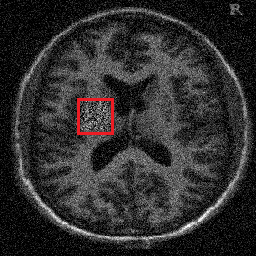

4.1. Uniform Gaussian noise

In this first experiment, we consider the denoising problem with brain scan images. The first set consists of images of pixels and Gaussian noise with zero mean and variance . The original and noisy images are shown in Figure 4.1. The domain decomposition-semismooth Newton algorithms run with the parameter values , , and . The results are shown in Figure 4.2. From the surface representation of , we can observe that is continuous and its shape is related to the one of the original image. In particular, the regularization is stronger in homogeneous regions in the image, and weaker where the image intensity undergoes variations on a smaller scale.

4.2. Non-uniform Gaussian noise

For this experiment we consider input images of size , with a Gaussian noise of on the whole domain and an additional Gaussian noise component of on some areas which are marked in red (see Figure 4.3). The parameter values used are , , and . The shape of is shown in Figure 4.4.